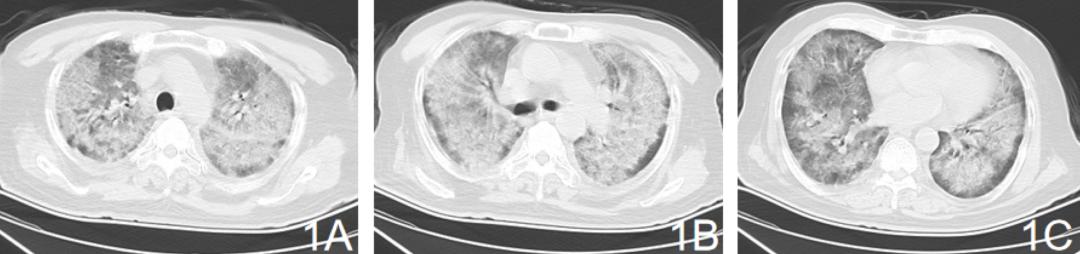

胸部CT:双肺弥漫性磨玻璃影及新旧不一的实变影,可见支气管气相【图1ABC】。

【图1】2020.3.14双肺弥漫性磨玻璃影及新旧不一的实变影

此患者发病时并没有主诉发热而是以意识不清、呼吸困难起病,极易造成误诊。但发病时肺部影像出现双肺弥漫分布的磨玻璃影,氧合指数小于100 mmHg,符合由肺源性引发的急性呼吸窘迫综合征(ARDS),其死亡率高达45% [4]。寻找肺炎的病因是本例患者关键所在。除外大量粉尘接触史所致此次发病,是新冠病毒还是流行季节如流感病毒或常见病毒?

经血抗体检测明确为腺病毒,两次腺病毒IgM阳性,符合腺病毒肺炎的诊断 [5]。Clark等人对21例社区获得性腺病毒肺炎患者的总结表明 [6],腺病毒肺炎通常表现为发热(90%)、咳嗽(80%)和气短(70%),可在数小数至数天内即发展为呼吸衰竭,高达67%的患者需要机械通气支持。死亡率高达24%。实验室检查通常发现白细胞减少、淋巴细胞减少、血小板减少和转氨酶升高。腺病毒肺炎在胸部CT上通常表现广泛间质病变、磨玻璃影、实变影或胸腔积液。部分患者在影像上可表现为肺叶实变,因此很难与细菌性肺炎相鉴别 [7,8]。